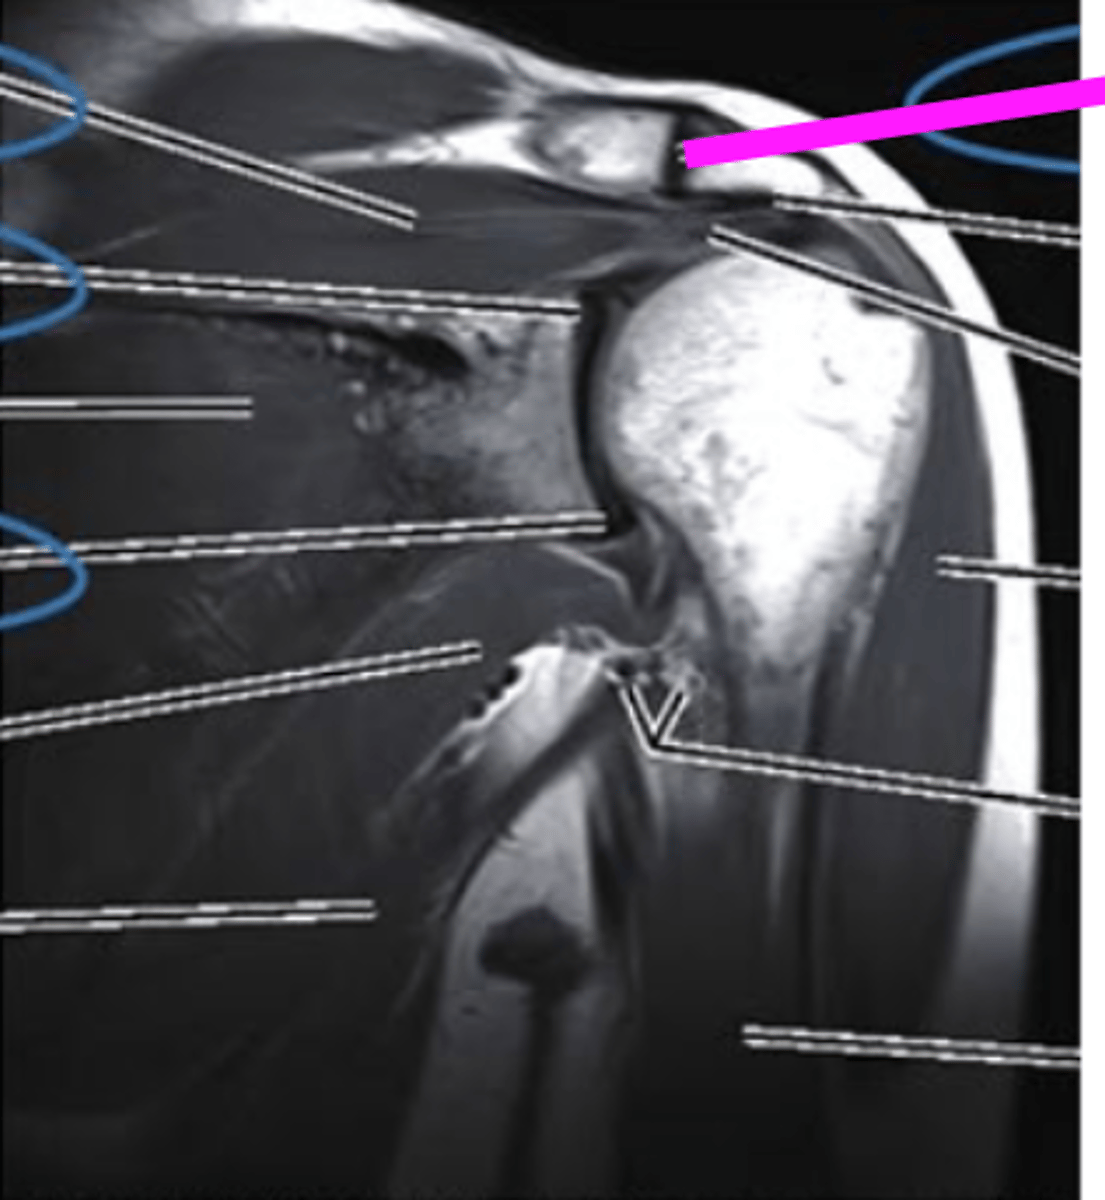

Coronal MRI

what imaging type and view is this?

AC joint

what does the pink line point to?

supraspinatus muscle

superior labrum

inferior labrum